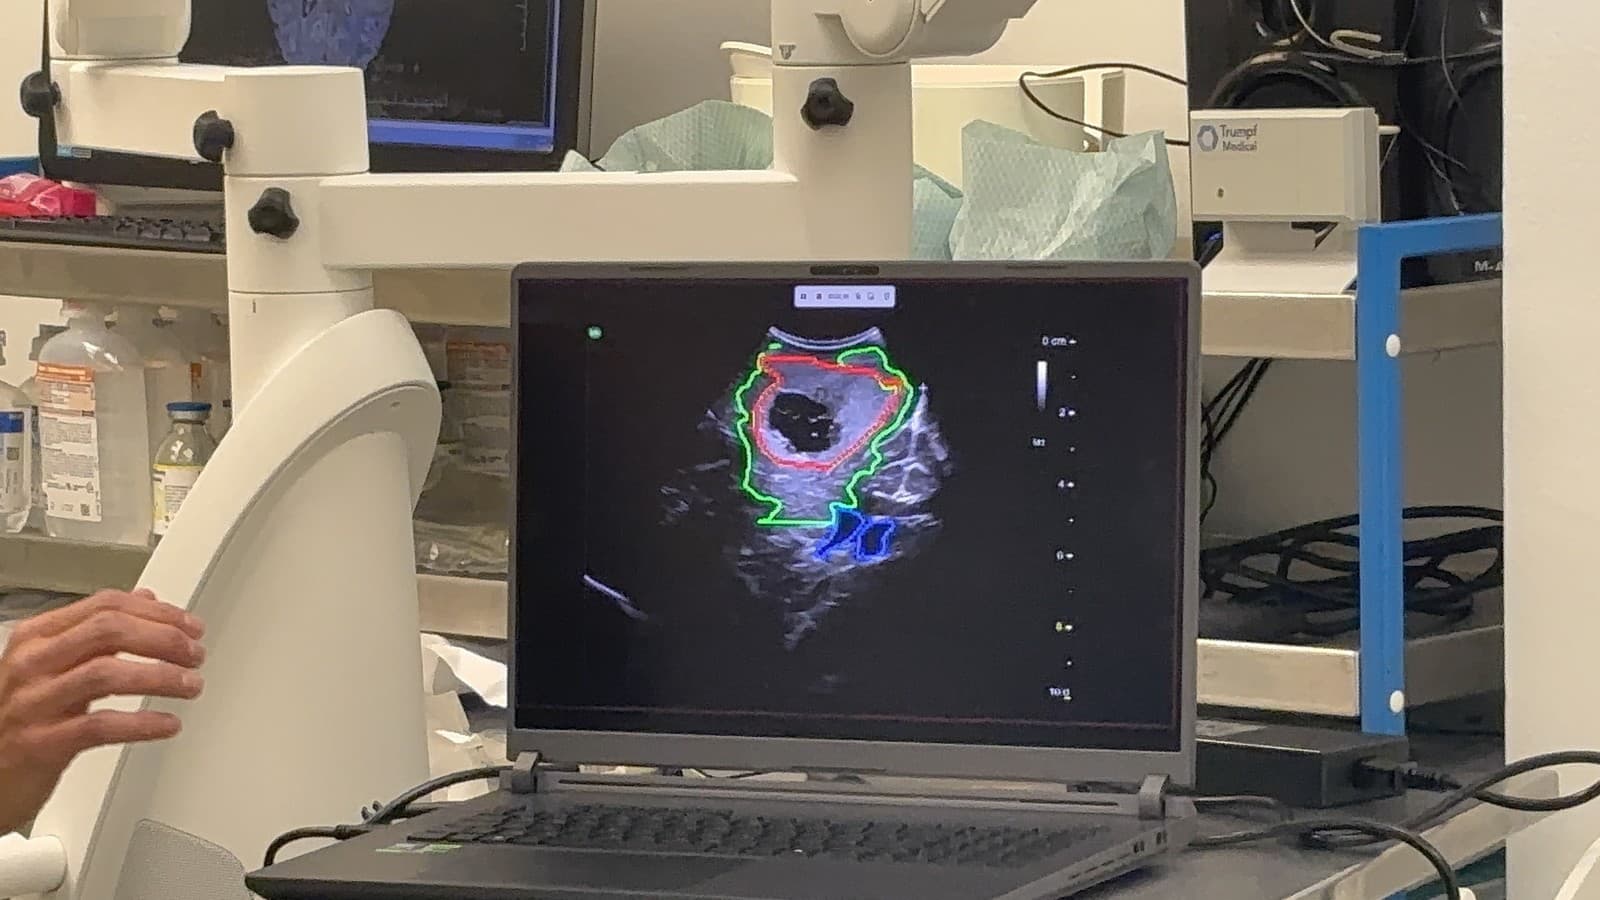

Model umelej inteligencie, ktorý vedci z Univerzitnej nemocnice vo Valladoloide vytvorili, dokáže podľa slov UNB na ultrazvukovom obraze mozgu priamo počas operácie zistiť pozíciu zvyškov nádoru, ktoré sú okom často nerozoznateľné. Ich identifikácia však významne napomáha k úspešnému výsledku operácie.

"Po tom, ako sa nedávno publikované výsledky našich operácií stali jedným z dôležitým podkladov pre zmenu najnovších amerických gajdlajnov operačnej liečby gliových nádorov mozgu, je oslovenie zo strany špičkového odborníka Dr. Santiaga Cepedu v krátkom čase už druhým významným ocenením našej práce," uviedol doc. Šteňo. "Prínos umelej inteligencie počas operácie nádoru mozgu sa nateraz javí ako jednoznačný, a pre celú našu kliniku je obrovským zážitkom byť priamo pri vývoji tejto fascinujúcej technológie, ktorá zmení budúcnosť neurochirurgie," dodal prednosta kliniky Andrej Šteňo.